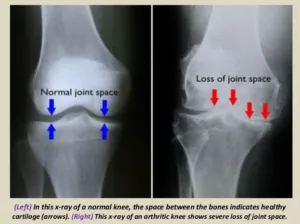

FIGURE: (i) healthy knee joint. (ii) arthritic knee joint with joint space narrowing (i.e. bone on bone)

Arthritis is one of the most common conditions that occurs with aging. In fact, after heart disease, it is the most common chronic condition that affects people all over the world. Specifically, a particular subset of arthritis, known as osteoarthritis, is the most common form of this condition. Arthritis occurs as the cartilage in our joints (e.g. knee, hip, ankle, shoulder) wears away which in turn leads to a process of inflammation, tissue breakdown, and reactive bone formation. You may have heard sayings such as “bone on bone”, “narrowing of the joint space” and so forth. If you compare joint space to the tread on a tire, the end result of the arthritic process is analogous to the tread on the tire that wears out over time with mileage. Similarly in the knee joint for example, as the cartilage wears out over time, joint space decreases.